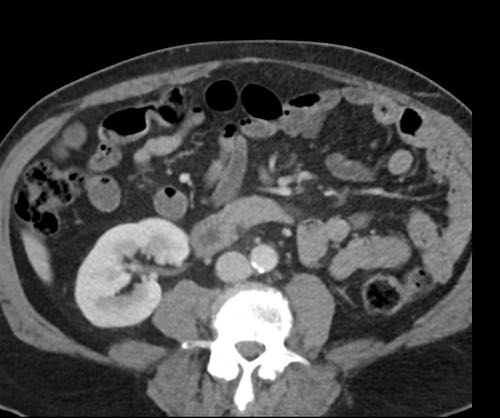

Cuộn xem ảnh CT

Ca lâm sàng 1

Cuộn qua các lát cắt.

Bạn có thể phát hiện tất cả các tổn thương cấy ghép phúc mạc không?

Bệnh nhân này đã được phẫu thuật và toàn bộ phúc mạc được ghi nhận phủ kín bởi các tổn thương u dạng kê.